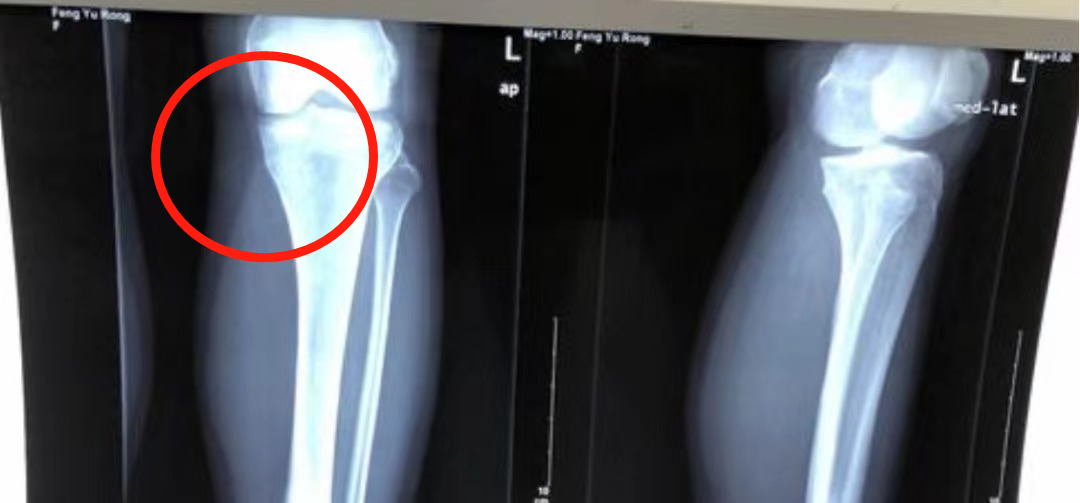

话说之前有姐妹在后台发图私信问一姐,膝盖内侧突出是什么原因。

一姐思来想去,觉得下图这种情况主要还是先天骨骼的问题。

有些姐妹的Q角天生比较大,会让膝关节存在外翻趋势。

如果膝盖区域的骨骼是下图这样的一个结合形态,那么膝盖就很有可能在外观上表现出一点内侧突出的形态。

一般这样的腿看起来就不是很直